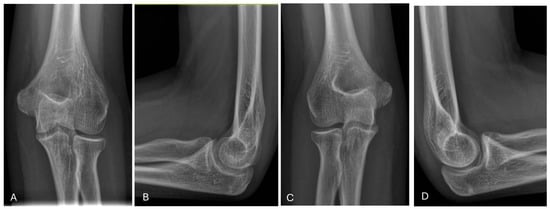

| Carrying Angle | 12.3° | 4.28 | 5–22° |

| Contralateral Carrying Angle | 12.3° | 3.87 | 5.9–20° |

| Baumann Angle | 78.9° | 13.5 | 60.4–112° |

| Contralateral Baumann Angle | 79.1° | 12.7 | 63–118.8° |